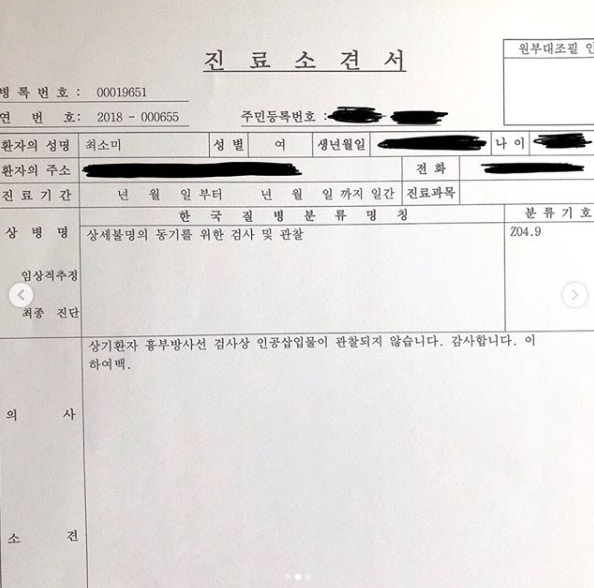

韓國人氣網紅 Choi Somi 外貌激似女星郭雪芙,因此有著「韓國郭雪芙」的封號,廣受臺灣粉絲喜愛,從不介意性感穿著的她,時常在網上分享自己的美照, 大方展露自己的傲人身曬,超惹火的上圍卻也為她招惹整形風波,面對網民質疑的聲音,去年,Choi Somi還因此在IG貼出胸部X光圖與醫師診斷書,證實自己的胸部是真的,大動作反擊也引發網友們對她的討論。

Choi Somi 胸部診斷書上寫著「沒有人工植入物」,也讓 Choi Somi 獲得清白,但當中還是有人抱持懷疑態度,認為診斷書可造假之疑慮。